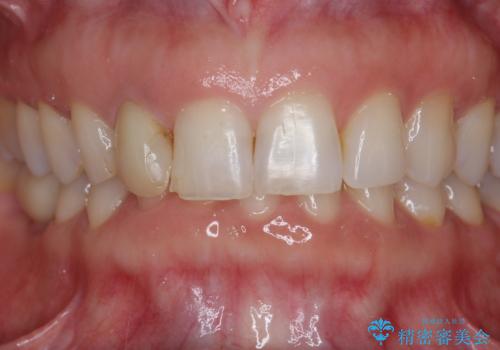

セラミック治療を行う前にきっちりと根管治療を行うことが長期的に持つ可能性を高めます。

- 天然歯を削ります

- 硬い素材は天然歯を傷つけてしまう場合があります

- かみ合わせや歯ぎしりが強すぎる方はセラミックが割れてしまう可能性があります